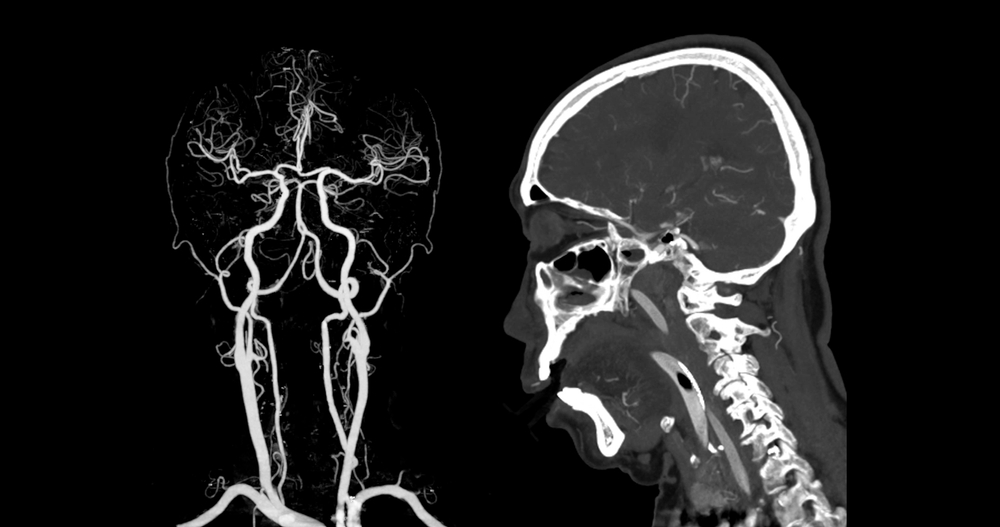

- Стол с пациентом въезжает в томограф. Доктор идет в комнату, расположенную за толстым стеклом. Включает устройство. Рабочая часть томографической установки вращается вокруг головы человека. Благодаря этому, формируется большое количество срезов с малым шагом. Они передаются на компьютер врача. Затем с помощью программы преобразуются в трехмерные проекции сосудов.

Итогом КТ головного мозга и сосудов становится развернутое заключение. В нем врач указывает состояние вен и артерий, их вид, строение, контуры, диаметр. Специалист указывает наличие патологических изменений. Отражает их важнейшие параметры: размер, расположение, очертания, характер поражения, степень инвазии, распространенность. Также доктор пишет заключение. Он не ставит диагноз и не назначает лечение. Указывает общие рекомендации.

КТ сосудов головного мозга с контрастом позволяет диагностировать:

Фотогалерея